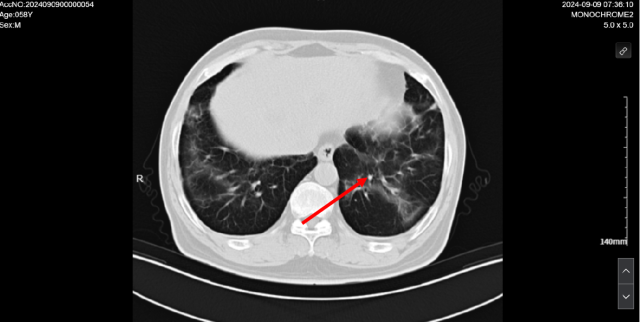

2024-07-17 CT

伏罗尼布治疗后,2024-09-09 复查 CT

1. 考虑双肺炎症改变,较前范围减小,建议复查

2. 双肺多发结节,较前减小。

3. 双肺多发纤维灶。

4. 心包积液。

5. 肝内多发低密度病变,结合病史,不除外转移瘤可能,较前部分减小:建议必要时 CT 增强扫描进一步检查。

6. 考虑:肝左叶囊肿。